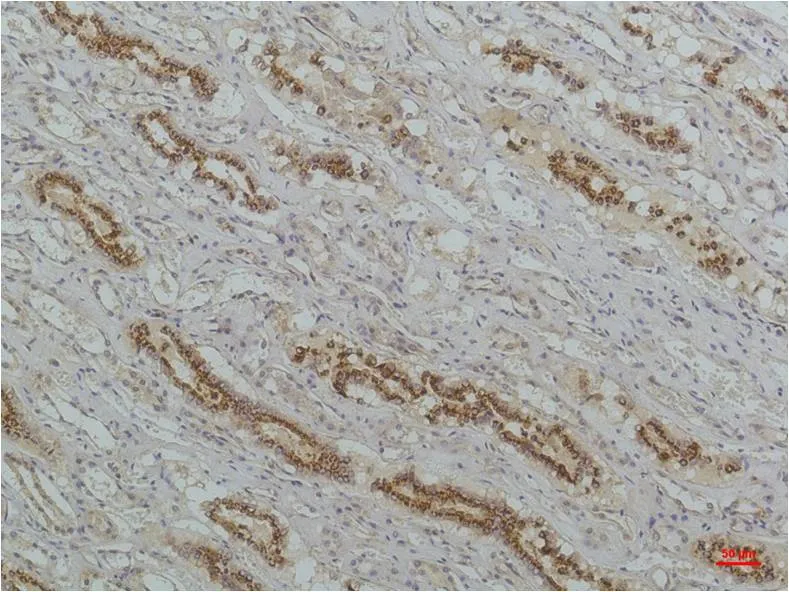

IKB beta (5H3) Mouse Monoclonal Antibody

Cat: AMM00735

Application:IHC-P

Reactivity:Human,Rat,Mouse

Conjugate:Unconjugated

Gene Name:NFKBIB